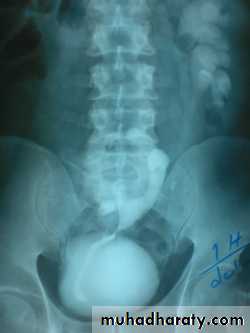

1- Mega ureter2- Retrocaval ureter3- PUJ obstruction 4- Double ureter5- Horse shoe kidney6- Ectopic pelvic kidney Bilateral Hydronephrosis7- Polycystic kidney 8- Copra head 9- Copra head 10- Ectopia vesica